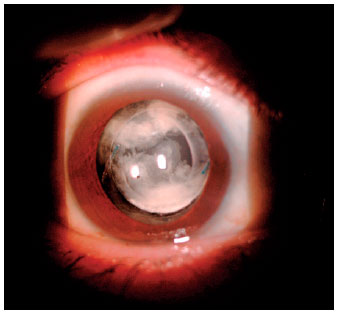

The slit-lamp anterior biomicroscopical examination of the right eye revealed a nonhyperemic conjunctiva; clear cornea, without anterior chamber cells; a topic IOL; and opaque material between the lens and the posterior capsule. Binocular indirect ophthalmoscopy to evaluate the posterior pole was impossible because of media opacities (Figures 1-2). The intraocular pressure measured at 13:00 hours using Goldmann tonometry was 14 mmHg in the right eye and 12 mmHg in the left eye.

The anterior segment of the same eye was also evaluated using anterior segment optical coherence tomography (Visante® Zeiss). Hyper-reflective material was found between the lens and posterior capsule, which had led to capsular distention. As the capsular bag was complete, we confirmed the diagnosis of CBS (Figure 3).